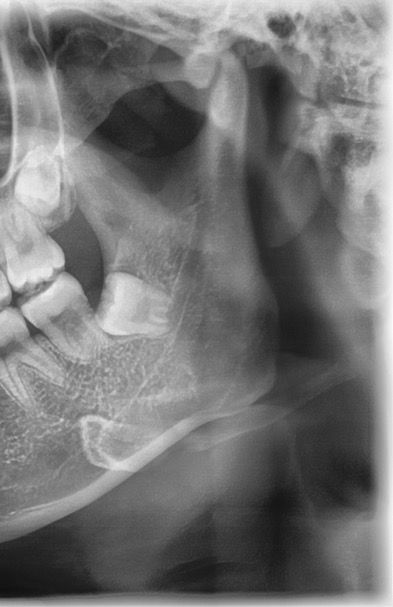

이런 경우 매복 사랑니 꼭 빼야할까요?

이때까지 교정하고 정기검진 10년 가까이 다니면서 사랑니 있다는 말은 따로 못 들어서 사랑니가 없는줄 알았어요

근데 새로운 치과에 치료받으러 갔다가 매복 사랑니가 있어서 아래쪽은 나중에 앞니 뿌리가 상해서 발치를 해야할 수도 있다고 발치 잘하는 병원가서 뽑으라는데 꼭 뽑아야하나요?

이때까지 사랑니가 있는줄도 모를정도로 문제가 없었는데...

• 1번 째 사진

사진에 보이는 사랑니는 특별한 이유가 잇지 않다면 발치를 안하셔도 될것같습니다. 걱정하지 않으셔도 될것같습니다.

사랑니가 완전히 매복되어 있는 경우에는 꼭 발치를 할 필요는 없고 검진만 주기적으로 하셔도 됩니다.

사랑니가 잇몸 안에 완전히 들어가 있다면 굳이 발치를 할 필요가 없습니다. 주기적으로 사랑의 주변에 문제가 발생하지 않는지 치과에서 검진을 받아보는 것이 좋습니다.

옆 어금니를 사랑니가 누르게되면 아주 천천히 뿌리흡수의 가능성도 있긴 합니다 다만 정확히 지금 겹치있는지는 파노라마 사진보고는 판단이 어렵습니다

현재 사랑니가 기울어져서 매복되어 있으며, 이경우 앞의 어금니를 서서히 상하게 합니다. 이를 방치시 나중에 앞의 어금니와 사랑니를 모두 발치해야하는 상황이 오게 되기에 가급적 빠른시일내에 사랑니를 발치하길 권합니다.